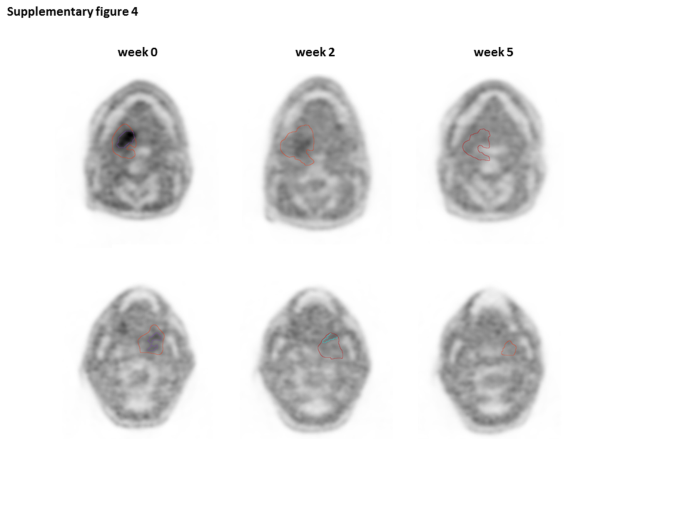

Supplementary figure 4:

figure 8

Representative images demonstrating the differential dynamics of tumor and hypoxic subvolumes during the course of chemoradiation. Time course of tumor volumes (red contours) and hypoxic tumor subvolumes (purple contours) from week 0 to 5 for a representative patient with early (week 0 to 2, upper panel) or delayed (week 2 to 5, lower panel) resolution of tumor hypoxia. (PNG 626 kb)